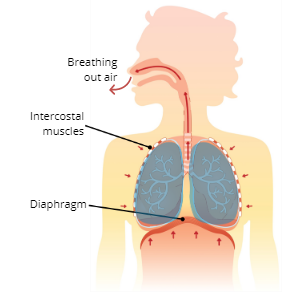

What are the 3 major respiratory muscles?

Diaphragm, External Intercostal Muscles, and Internal Intercostal Muscles

Diaphragm

a dome-shaped muscle below the lungs that separate the thoracic and abdominal cavity

Internal Intercostal Muscles

pull ribs downwards and inwards

Exhalation (Expiration)

Explain the Process of Exhalation (Expiration

The intercostal muscles and diaphragm relax, which causes the thoracic cavity to reduce in size which decreases lung volume, this then creates pressure that pushes air out of the lungs